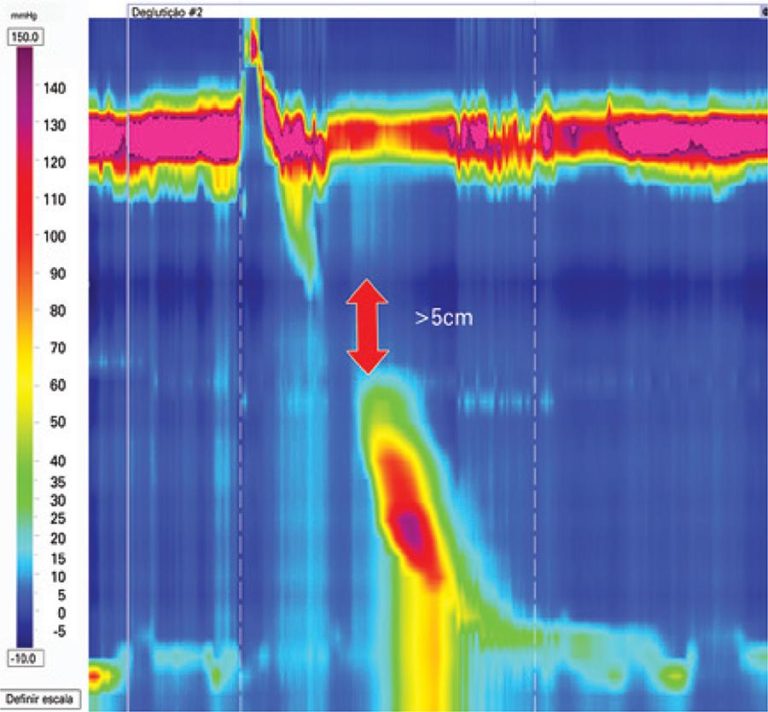

A manometria de alta resolução mudou vários paradigmas da motilidade digestiva. A Classificação de Chicago, na versão 3.0, definiu critérios manométricos para as doenças da motilidade esofagiana. O presente artigo é um atlas das dismotilidades descritas. Tipos de acalásia, obstrução ao nível da junção esofagogástrica, contrações ausentes, espasmo esofagiano distal, esôfago hipercontrátil, motilidade esofagiana ineficaz e peristalse fragmentada são mostradas em traçados de manometria de alta resolução.